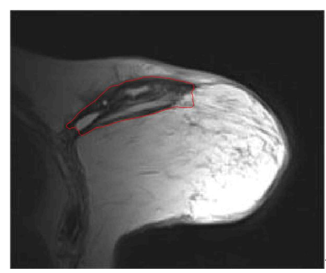

After several parameter adjustments, applying the DRLSE algorithm to this new medical image produced a less precise results in terms of segmenting the structures of interest. This observation prompted us to consider other approaches to improve segmentation quality. Figure 9 shows the segmentation result on breast MRI with α=1.5, λ=5, and μ=0.02.

a-Initial contour

b-Segmented image

Figure 9. Segmentation result with the DRLSE algorithm